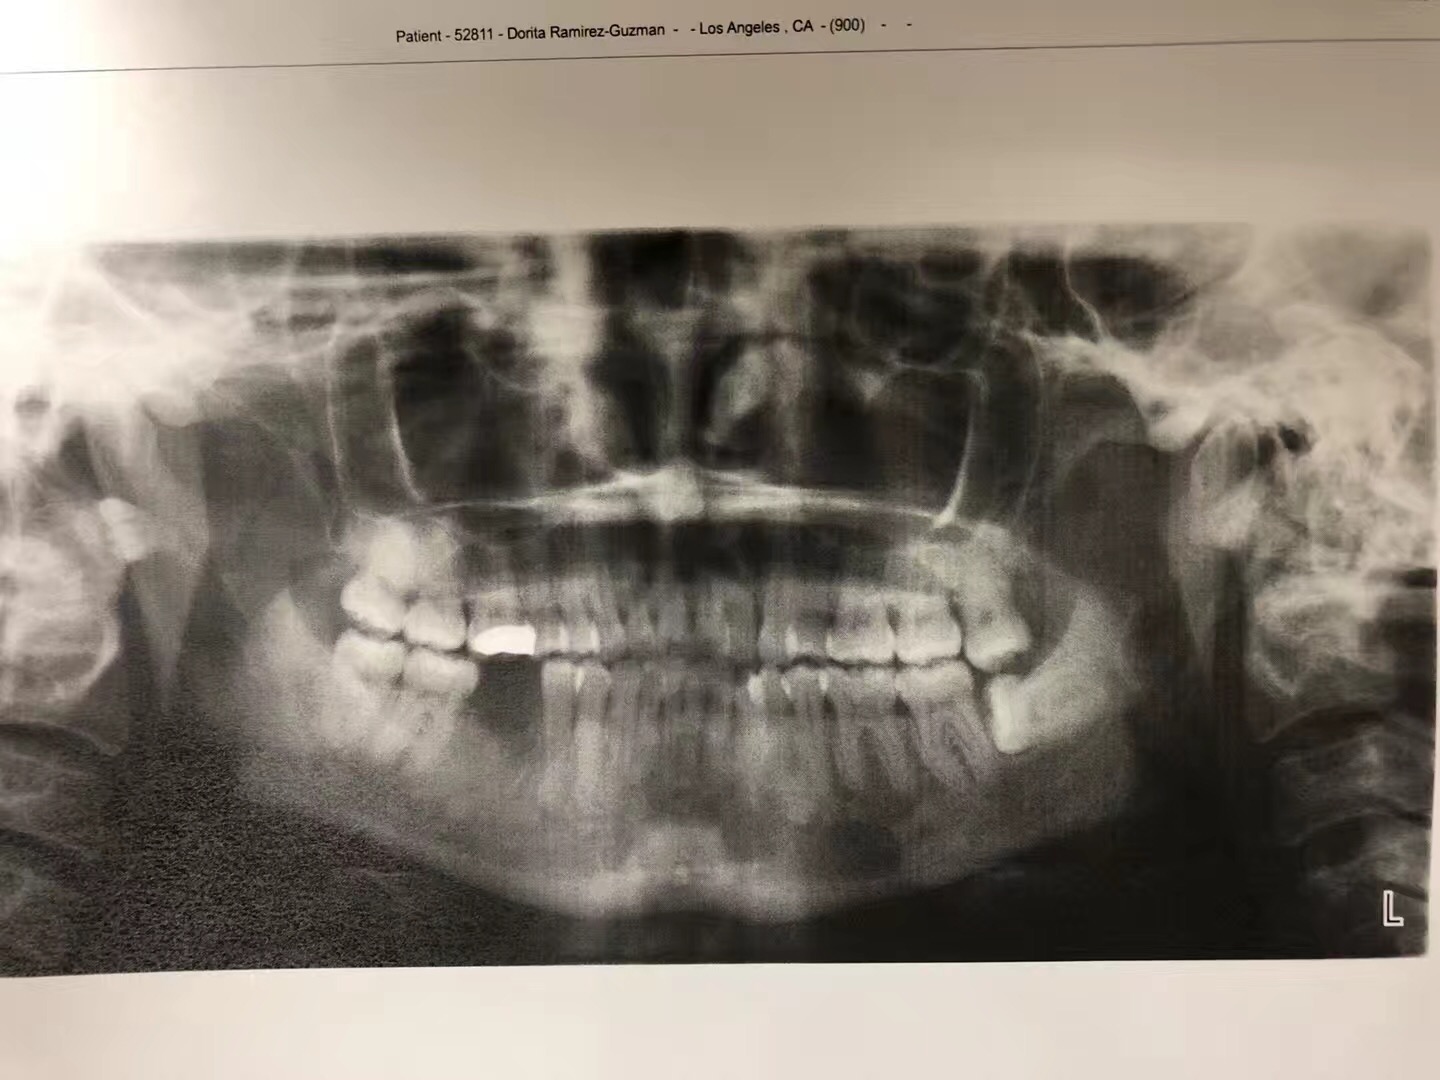

我是林俊男牙醫博士。今天讲述的是一位墨西哥裔年仅37岁乳腺癌第四期患者的实例,也就是说她的病情已经轉移到腦部和骨頭。

她从2011年患病到現在,一直在注射化療藥物(IV Zometa)。由于大多数癌症病人在接受静脉注射二磷酸盐药物帕米膦酸钠和唑来磷酸之后,使用了二磷酸盐治疗的患者可能会发生一种严重的下颌骨不良反应,称为下颌骨坏死。

2016年,她感觉第一大臼齒的地方很疼痛去看了一般的牙醫,这位牙醫立即幫她拔了疼痛的牙齒,结果她的牙根却留在牙糟裏。后來,她来到我們南加大醫院的口腔外科,我的住院醫生见状,幫她把牙根拔了,結果引起骨壞死。这一年多来,住院醫生只有開消炎藥和漱口水給她,但一直未见好转,后来,住院醫生把这位患者病情告诉我,希望我能幫她。我了解病情后,若按照常规治疗,效果不明显。我采用了自己研發的新藥,第一次病人需要在诊所注射,之後,再把藥交給病人,譲病人携帶回家自己打。二個星期後,病人回診,骨頭已經好了,而且還長的和之前一样。她见到我激动的说,林医生是我的救命恩人。